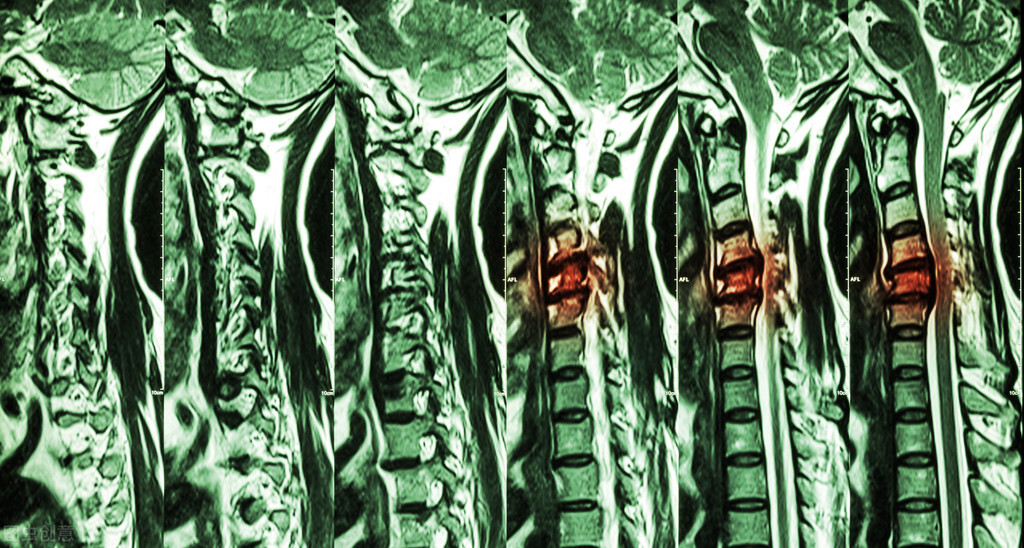

今天我们来说一下神经根型颈椎病,中医上也叫项痹病,咱们点个关注往下看。

神经根型颈椎病是颈椎病里最常见的一种类型,常与其他类型合并存在。据统计,颈椎病的发病率约为3.8%~17.6%,其中约60%~70%患者表现为神经根病变症状。